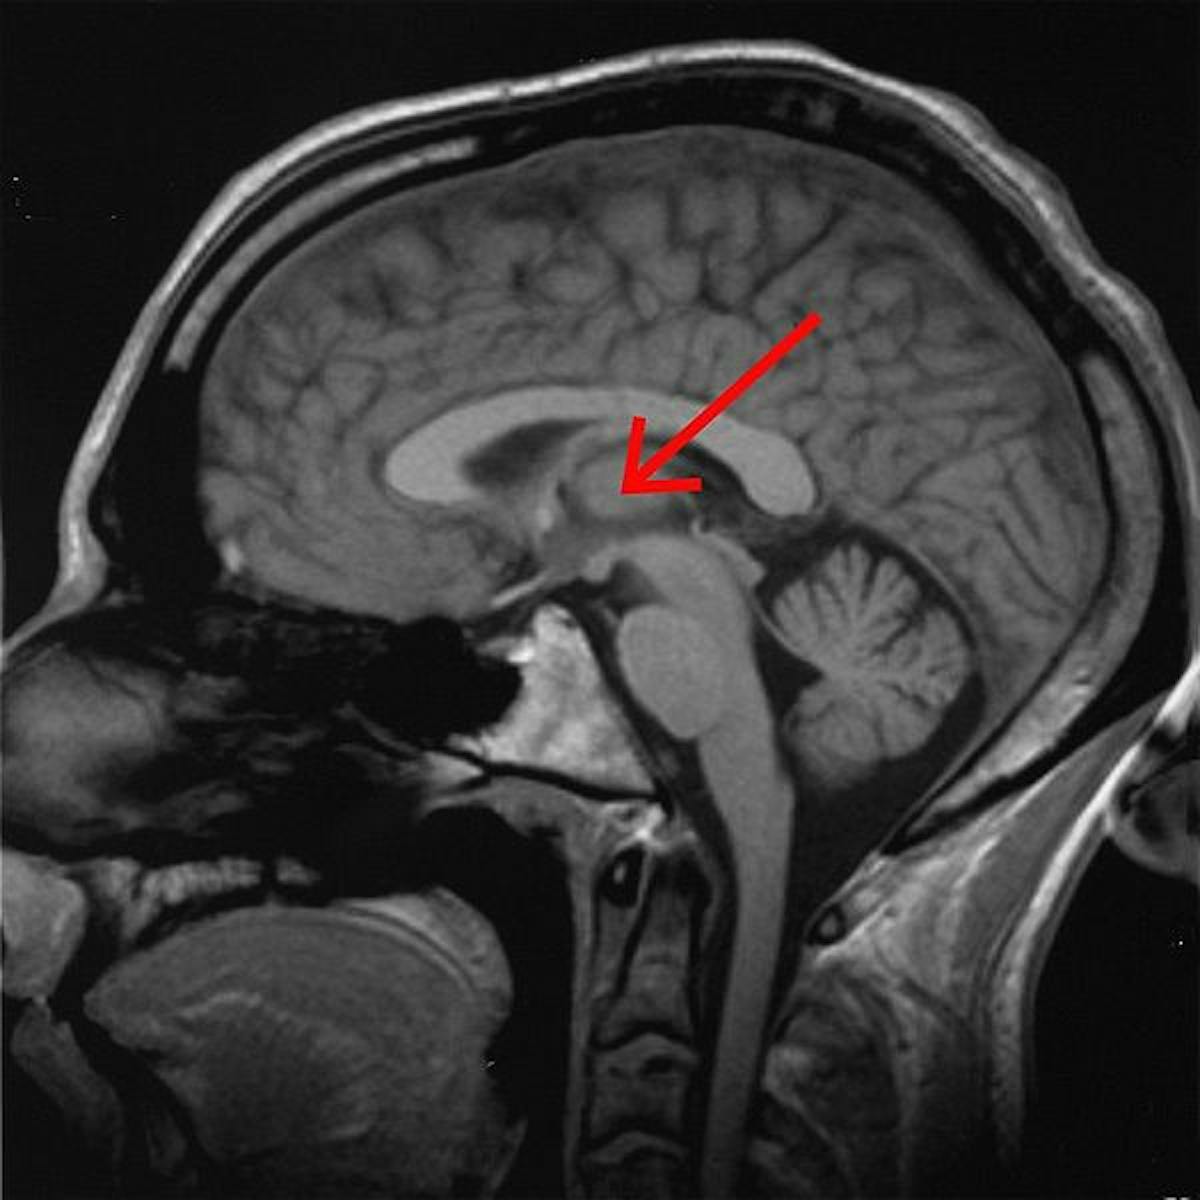

The thalamus acts like a kind of sensory gatekeeper. As sensory information from the environment comes in, the thalamus filters out the unimportant bits, allowing the brain to process and react appropriately to the information that demands attention — like a car horn beeping to warn you not to jaywalk, or a flashing warning light.

By looking at the participants’ brain activity during the LSD trip, the researchers found that the drug reduces the activity in a neural circuit — specifically the striatum’s influence on the thalamus. That opened up the thalamic filter to a specific part of the cortex called the posterior cingulate cortex.

“In particular, the present results pinpoint the role of the thalamus–PCC connection for the effects of psychedelics,” they wrote.